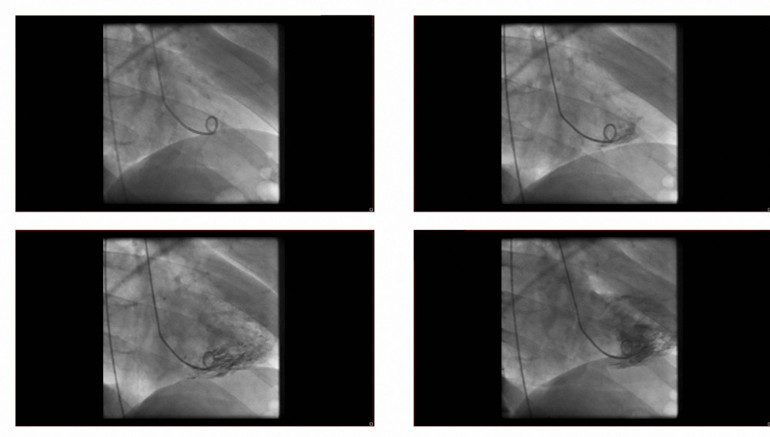

Türk sanat müziğinin efsane ismi Muazzez Abacı, geçtiğimiz haftalarda Amerika’daki evinde kalp krizi geçirmiş, sonrasında anjiyo olmuş ve stent takılmıştı.

Operasyonun ardından yaşanan komplikasyon nedeniyle yoğun bakıma alınan Abacı’nın menajeri Taner Budak, sanatçının son sağlık durumuyla ilgili açıklamasında ‘Anjiyo sırasında verilen kontrastlı sıvının böbreklerinde sorun yarattığını, böbrekleri görevini tam anlamıyla yapamadığı için ciğerlerinin su topladığını, bu sebeple nefes alma sorununun ortaya çıktığını’ söylemişti.

Yapılan bu açıklamalara göre Abacı aslında yaşadığı kalp krizi nedeniyle değil anjiyo esnasında verilen kontrastlı sıvının böbreklere verdiği hasar nedeniyle yoğun bakıma alınmıştı. Usta sanatçının vefat haberi ‘Abacı’nın ölümüne kontrastlı sıvı mı neden oldu?’ sorusunu akıllara getirdi.